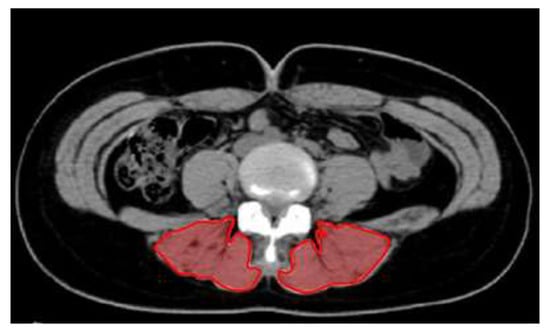

2.4. Cross-Sectional Area

| CSA (cm2) | Pre | 20.30 ± 4.74 | 15.55 ± 2.53 | 19.83 ± 3.45 | 5.519 ** | a > c * b > c * |

| Post | 24.53 ± 4.34 ††† | 23.78 ± 2.49 ††† | 19.96 ± 3.75 | |||